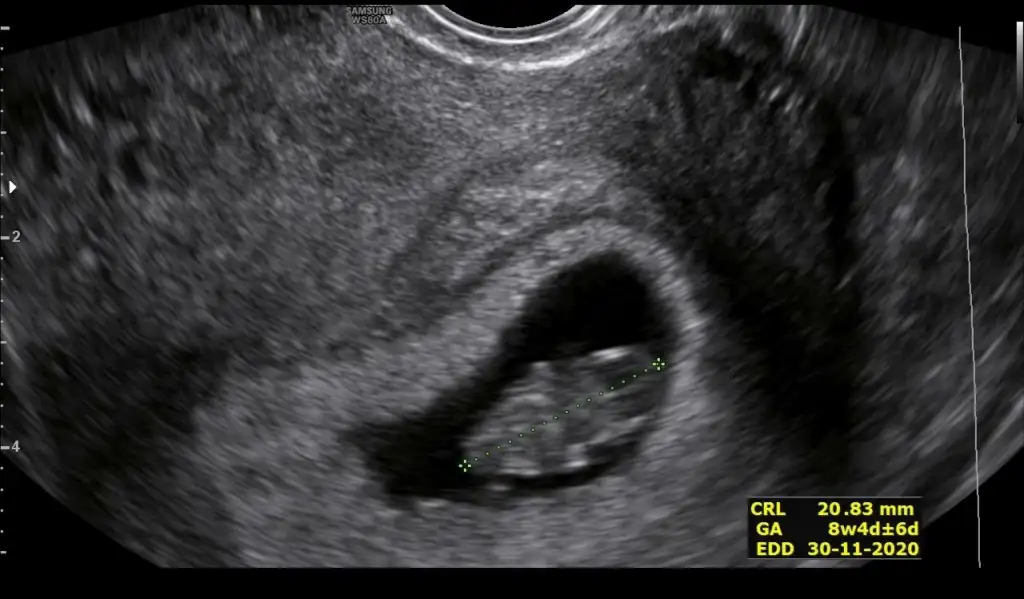

Benim ultrason kağıtlarım Bi türlü düzgün çıkmıyor 9+6 günlük kanama alanımda hala var tahminde yapılmaz bundan

Eklentiler

• IMG_20200507_120238.webp

13,2 KB · Görüntüleme: 67

Sağol canım ben doktordan geldim gelişimi güzel 9+6olmuş ama kanama alanım hala varmış dünde hafif kanamam gene başladı

Bende öyleyim benim kanama alanı kesenin altında gözüküyor attım fotosunu doktor aslında olmaması lazım kanamanın ama yinede bebek iyi gelişiyor dedi hatta 2 gün önden gidiyor